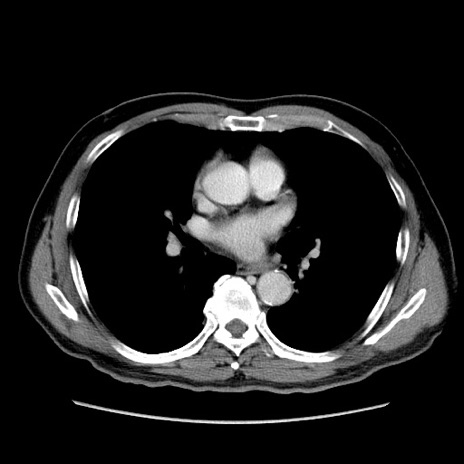

症例34(横断像)

【症例】60歳代 男性

【主訴】右鼠径部膨隆

【現病歴】1年程前より右鼠径部膨隆あり。自己にて還納可能だったため放置していた。3時間前より右鼠径部の脱出を認め、還納困難となり受診。

【既往歴】高血圧

【身体所見】右鼠径部に小児頭大の膨隆あり。弾性硬であり、用手還納は困難。左鼠径部にも膨隆を認める。脱出はなし。

【データ】WBC 15500、CRP 測定なし